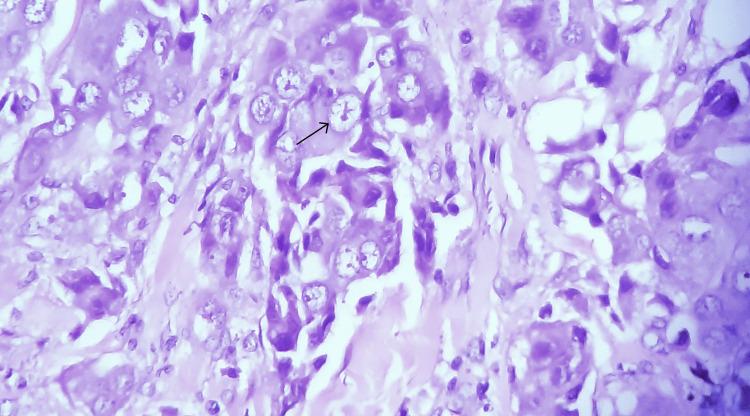

A rare inflammatory breast disorder called lymphocytic mastitis is characterized by lymphocyte infiltrates in the mammary parenchyma. Due to their rarity, incidental observations of invasive ductal carcinoma in lymphocytic mastitis present diagnostic and management challenges. We present a case of a 52-year-old female with a history of painfully swollen breasts for three months who underwent a core needle biopsy, consistent with lymphocytic mastitis on histopathology. Due to persistent and worsening symptoms, a mastectomy was performed. During the examination, an incidental finding of infiltrating ductal carcinoma was identified in the mastectomy specimen. This unexpected discovery led to further investigations and altered the patient's treatment plan. The detection of invasive ductal carcinoma in the presence of lymphocytic mastitis highlights the importance of continuous surveillance and thorough examination. In the circumstances of lymphocytic mastitis, it is vital to take the likelihood of concurrent malignancy into account, especially when symptoms persist or reappear after appropriate management. This case report seeks to raise awareness among physicians of this exceptional association and drive further research that will explain its pathophysiology while enhancing management strategies.